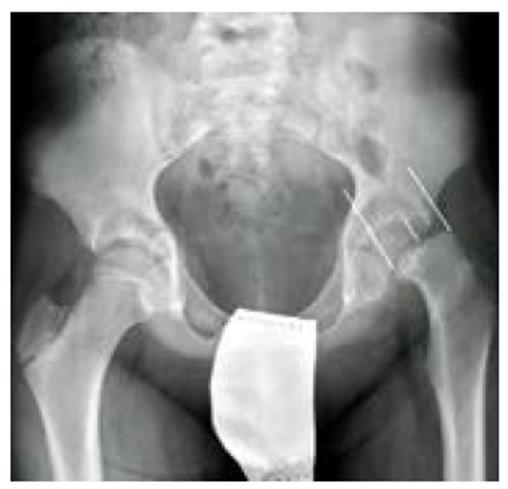

Figura 3 Radiografía A-P de pelvis con el porcentaje de desplazamiento de la epífisis sobre la anchura de la metáfisis.

La EFP también puede clasificarse radiológicamente según el porcentaje de desplazamiento de la cabeza femoral respecto al cuello, siendo leve cuando el desplazamiento es menor al 33 %, moderado cuando el desplazamiento está entre el 33 % y el 50 % y severo si tenemos un desplazamiento mayor al 50 % (Figura 3). El otro método de clasificación es el descrito por Southwick, el cual depende de la magnitud del ángulo epifisariometafisario en la proyección lateral; este se obtiene trazando una lin ea paralela al cartílago de crecimiento de la cabeza femoral. Se dibuja una perpendicular a esta linea y luego se traza una linea que sigue el eje del cuello femoral. El angulo formado por estas dos últimas líneas determina el grado de desplazamiento comparándose con la cadera sana, y puede clasificarse como leve cuando el angulo es menor a 30 °; moderado, si el angulo esta entre 30 ° y 50 °; y grave, cuando es mayor a 50 ° (Figura 4) 15,17.